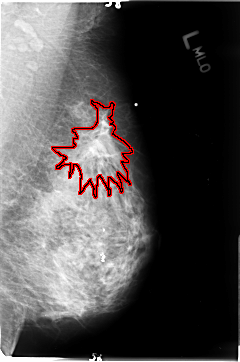

FILE: B_3048_1.LEFT_CC.OVERLAY

TOTAL_ABNORMALITIES 1

ABNORMALITY 1

LESION_TYPE MASS SHAPE IRREGULAR-ARCHITECTURAL_DISTORTION MARGINS ILL_DEFINED-SPICULATED

ASSESSMENT 4

SUBTLETY 4

PATHOLOGY MALIGNANT

TOTAL_OUTLINES 1

BOUNDARY